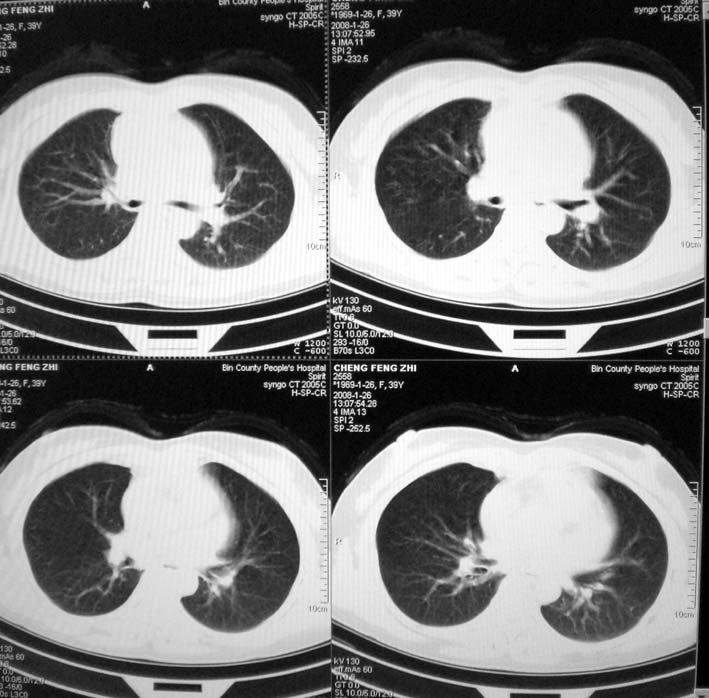

以下是引用guoke在2008-1-27 14:15:00的发言:[br]纵隔增宽,纵隔内血管境界不清,心包积液,考虑纵隔淋巴瘤.[br]

以下是引用随光逐影在2008-1-27 15:52:00的发言:[br]1)考虑为:淋巴瘤。建议:行进一步检查。2)心包积液。